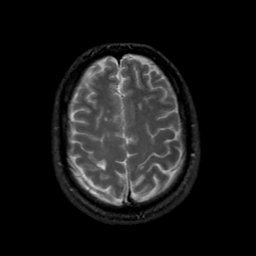

MR Study #18, July 21, 1991 -- Slice #39